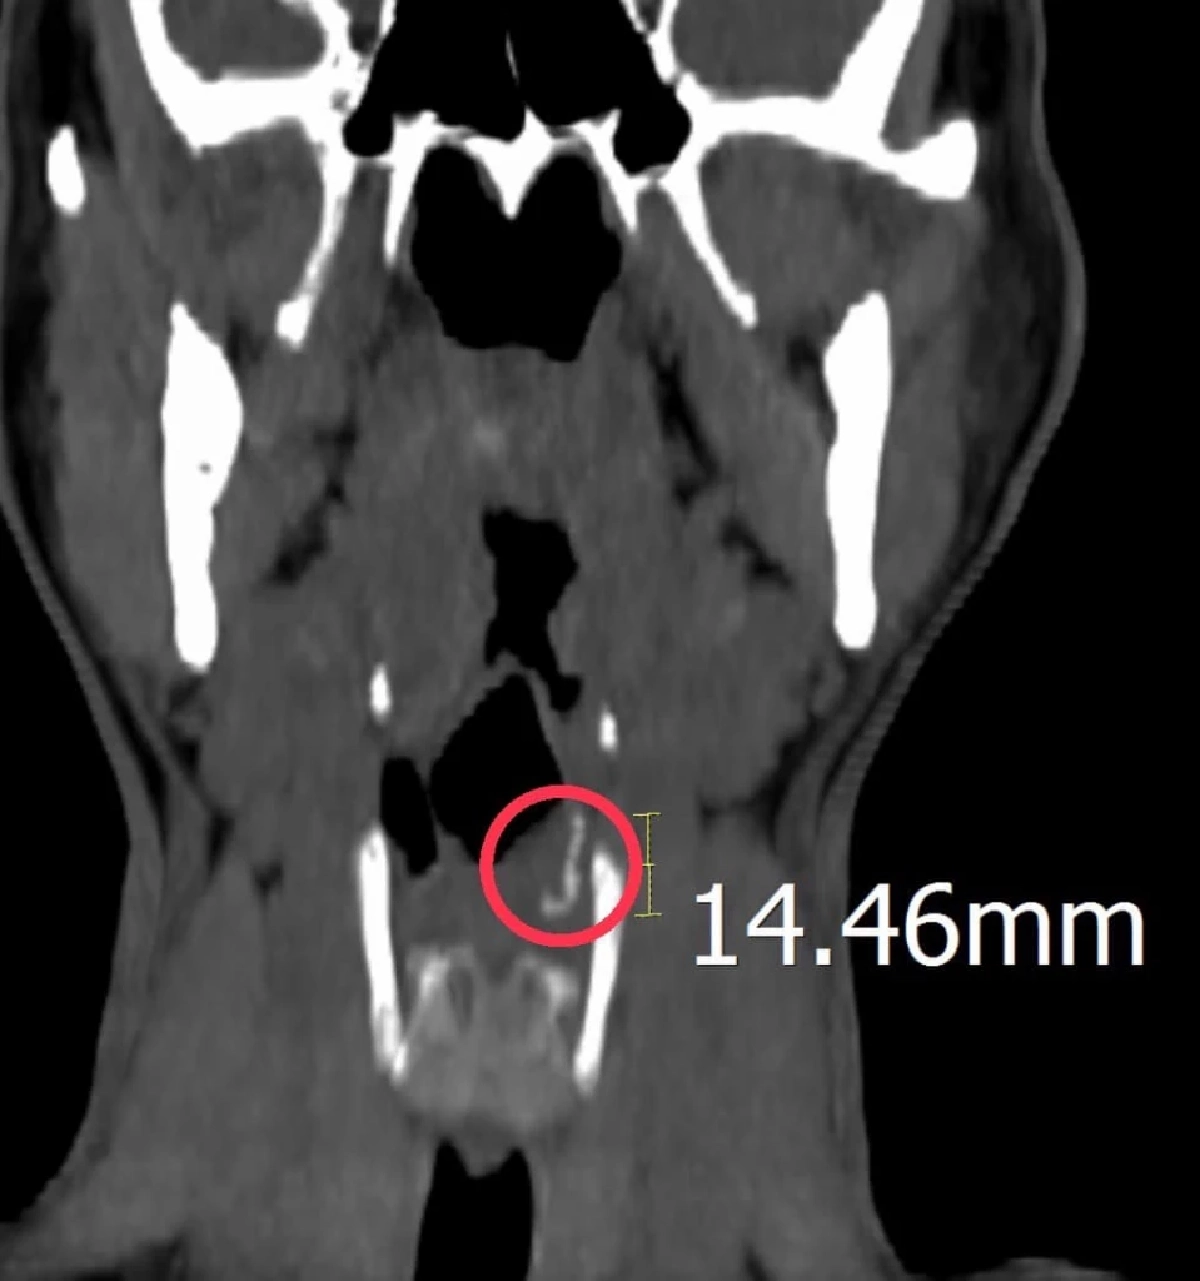

แพทย์ ห้องฉุกเฉิน ใช้เครื่องมือส่องใน ลำคอ ก็ไม่เห็นสิ่งแปลกปลอม จึงส่งตรวจเอกซเรย์คอมพิวเตอร์ส่วนลำคอ รังสีแพทย์มองเห็นภาพรังสี อ่านผลว่า มีสิ่งแปลกปลอมคล้ายโลหะขนาดยาวประมาณ 1.46 เซนติเมตร แทงฝังลึกในส่วนลำคอ ส่วนลึกใกล้ฝาปิดกล่องเสียง จึงรับผู้ป่วยไว้ในโรงพยาบาล ปรึกษาแพทย์ผู้เชี่ยวชาญด้าน หู คอ จมูก เพื่อนำเข้าห้องผ่าตัดส่องกล้อง ชนิดพิเศษ ด้วยการดมยาสลบไปด้วย เนื่องจากผู้ป่วยมีอาการปวดค่อนข้างมากและเพื่อป้องกันการสำลักอาหาร ในระหว่างส่องกล้อง

เมื่อส่องกล้องเข้าไป เจอชิ้นส่วน "ฝอยเหล็กขัดหม้อ" ทิ่มแทงฝังลึกใน ลำคอ ส่วนที่เรียกว่า pyriform sinus ด้านซ้าย ผ่าตัด เอาออกมาได้สำเร็จ หากปล่อยทิ้งไว้เนิ่นนาน นอกจากอาการปวดที่รุนแรงมากขึ้น จะติดเชื้อรุนแรงตามมาได้